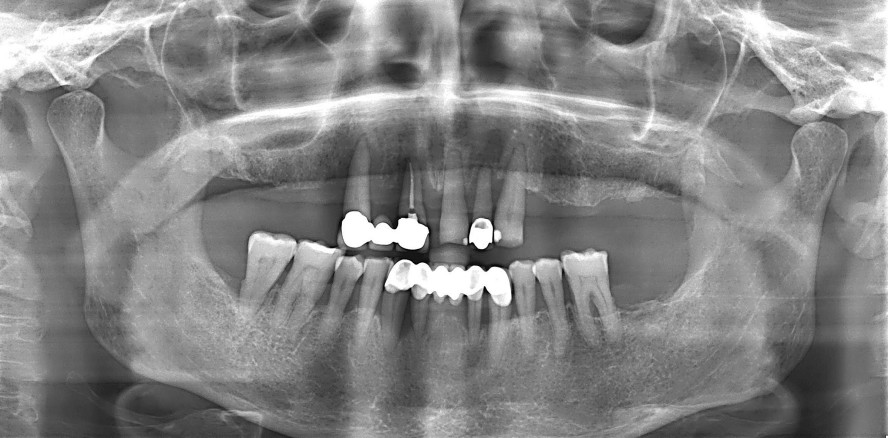

Anamnestisch berichtete die Patientin von täglichen Rauchgewohnheiten (< 10 Zigaretten/Tag), einer hohen beruflichen Stressbelastung (Selbstständigkeit) sowie einer inkonsequenten zahnärztlichen Überwachung, hervorgerufen durch ihre Angst. Die klinische Ausgangssituation bei Erstaufnahme ist in den Abbildungen 1 bis 3 dargestellt und wird von der röntgenologischen Aufnahme in Abbildung 4 ergänzt. Nach klinischer Befundung und radiologischer Auswertung wurde hier gemäß neuer Klassifikation eine generalisierte Parodontitis im Stadium IV, Grad C diagnostiziert.

Das postoperative Röntgenbild (Abb. 14) stellt die inserierten Implantate und die Ausgangslage für die weitere prothetische Versorgung dar. Das weitere Vorgehen erfolgte unter Zuhilfenahme des COMFOUR® Systems. Mit diesem kann eine bedingt abnehmbare Prothetik geschaffen werden, die mittels Verschraubung im parodontal kompromittiertem Gebiss eine Abnahme der prothetischen Versorgung ermöglicht, aber auch dem Patientenwunsch nach einer festen Versorgung entspricht (Abb. 15).